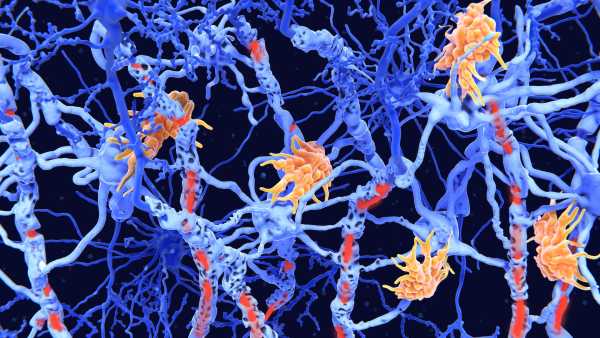

Стикаючись з інфекцією, ці «гуманізовані» миші виробляють імунні клітини, що імітують структуру та різноманітність імунних клітин, що виробляються людьми. Дослідники виявили, що коли їм вводять хімічну речовину, яка викликає поширене запалення в організмі, у мишей розвивається варіант аутоімунного захворювання – вовчака, який дуже схожий на той, що спостерігається у людей.

Однак, роками дослідники намагалися створити гуманізованих мишей, які б точно реагували на інфекцію так само, як і люди. Попередні спроби призвели до наближених моделей імунної системи людини, але їм бракує певних людських рис, йдеться у заяві команди, яка стоїть за новою статтею.

Після введення людського естрогену миші почали виробляти безліч людських імунних клітин. Серед них були Т-клітини, які безпосередньо атакують мікроби, та В-клітини, що виробляють антитіла, що знищують бактерії та допомагають позначити патогени для знищення.